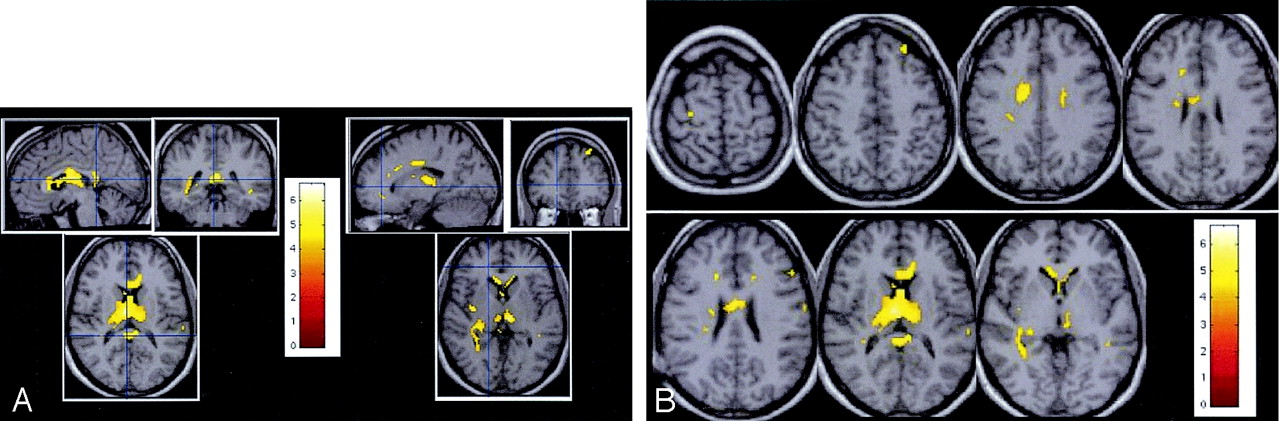

Statistical t test comparison between brain MTR maps of patients and control subjects are reported in Figure 1 and Table 3. MTR abnormalities were observed in both white and gray matter.

Statistical mapping analysis. Patterns of significant MTR abnormalities are observed inside the corpus callosum, bilateral occipitofrontal fascicles, right fornix, right parietal white matter, external capsule, right SLF, right ILF, optica radiata, parietal white matter, right cingulum, bilateral thalamus, bilateral caudate, right insula, and the left BA8.

A, Multiplanar images of MTR decrease observed in patients with CISSMS compared with control subjects.

B, Transverse images of MTR decrease observed in patients with CISSMS compared with control subjects.

In the white matter, low MTR values were observed in the corpus callosum, right occipitofrontal fascicles, right fornix, right parietal white matter, external capsule, right superior longitudinal fasciculus (SLF), right inferior longitudinal fasciculus (ILF), right optica radiata, and right cingulum.

In the gray matter, MTR abnormalities in the patients were located in the bilateral thalamus, bilateral caudate, right insula, and left Brodmann area (BA) 8. Abnormalities observed in the left BA40, left BA4, bilateral BA21, and right BA6 did not survive to spatial extent correction.